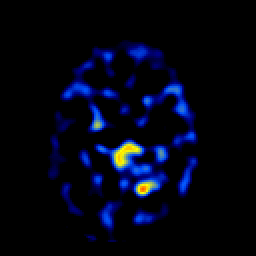

SPECT TL Study #6 -- Slice #43

[Home][Help][Clinical][Tour 1][Tour 2][Tour 3] Slice 43